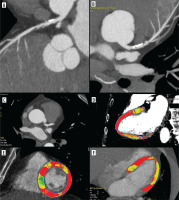

Figure 2

Coronary computed tomography angiography (CCTA) and dynamic computed tomography perfusion (CTP) scans from a 58-year-old male with a history of reduced exercise tolerance and shortness of breath. The patient underwent a comprehensive CT evaluation, including calcium scoring, CCTA, and dynamic stress CTP. The calcium score was 228 AU (80 mm3), consistent with moderate calcification (CAC-DRS A2 N2). Coronary CT angiography identified a 60-70% stenosis in the proximal-to-mid left anterior descending artery (LAD) (A-C). Dynamic stress CTP with regadenoson revealed reduced blood flow in the basal anterior and inferior-septal segments; mid anterolateral, inferolateral, inferior, and septal border zones; and the apical lateral segment. These findings indicated stress-induced ischaemia, predominantly affecting the LAD territory (D-F). Invasive coronary angiography confirmed 60–70% stenosis in the proximal-to-mid LAD. Based on the CTP findings of significant ischaemia, the patient was deemed suitable for ad hoc PCI targeting the LAD stenosis. Dynamic CTP Color-coding: Normal stress myocardial blood flow (MBF) is shown in red, and ischaemic regions (MBF < 100 ml/100 g/min) are depicted in blue